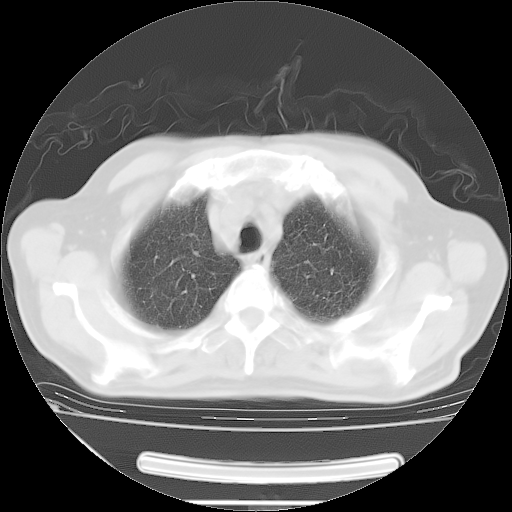

胸腹部CT,诊断意见:左上肺叶钙化灶、左侧胸膜局限性增厚并钙化、胆囊炎。描述部分肺组织呈磨玻璃样改变。